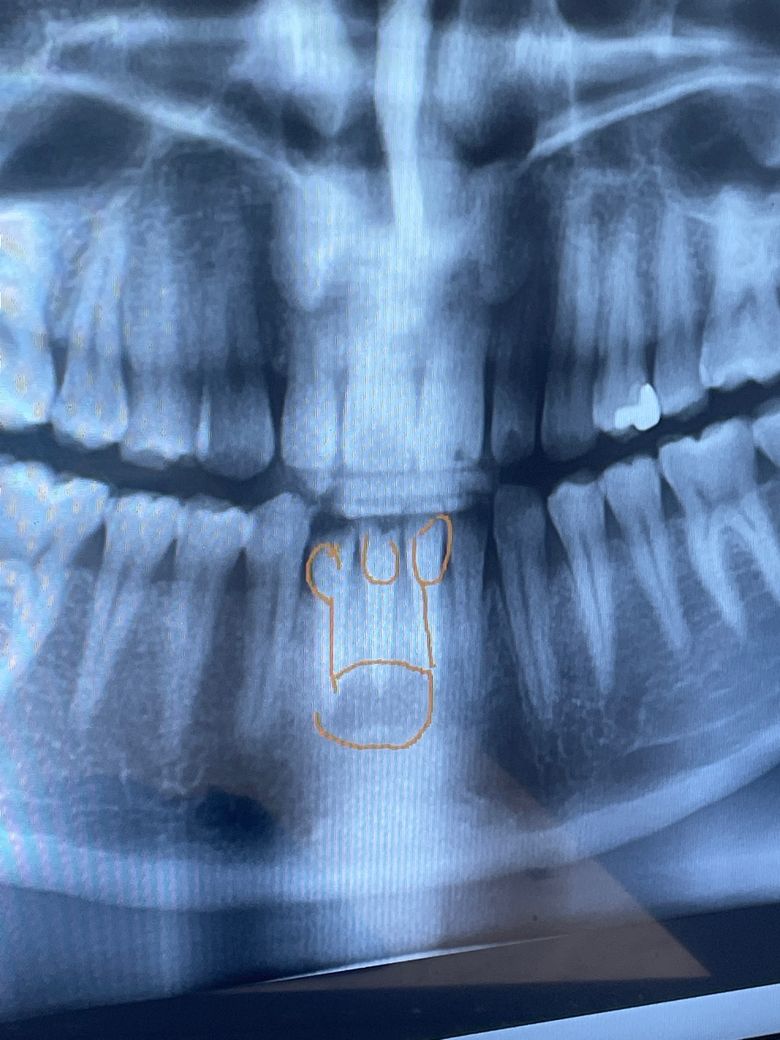

앞니 치아 뿌리에 염증이 크게 있어서 잇몸뼈가 많이 녹았을거라고 합니다 그래서 가운대 표시한 이빨이 흔들려서 발치를 하고 양쪽 치아를 신경치료후 브릿지를 한다는데 염증이 잇몸겉으로 멍우리 만져지듯이 튀어나와있습니다 임시 치아가 나오는날에 치료를 하신다 했는데 혹시 염증때문에 통증이 큰데 임시 방편은 없을까요 ㅠㅠ 그리고 이빨을 발치를 하면 염증이 줄어들까요 아니면 따로 긁어내는 수술을 해야하는걸까용

현재 통증으로 인해 불편감이 있는 경우 소염진통제를 약국에서 구매하여 복용을 하는 것이 증상완화에 도움이 됩니다. 발치를 하는 경우에는 염증이 줄어들게 됩니다.

통증이 심하다면 얼음팩 하시고 진통제 드시면 도움이 됩니다. 발치를 할 때 염증도 같이 긁어내기 때문에 발치후엔 염증도 줄어듭니다.

임시 방편은 진통제 복용 정도밖에는 뾰족한 수가 없습니다. 발치하고 나서 남은 염증 조직을 제거하는 과정도 함께 진행됩니다.